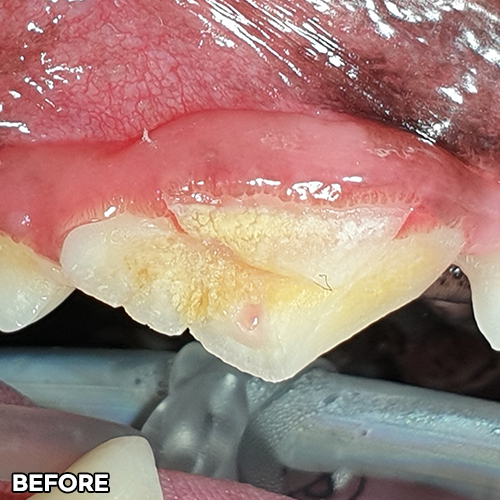

강아지스케일링 및 치주치료! - 자기치아살리는 힐링힐스동물치과 -